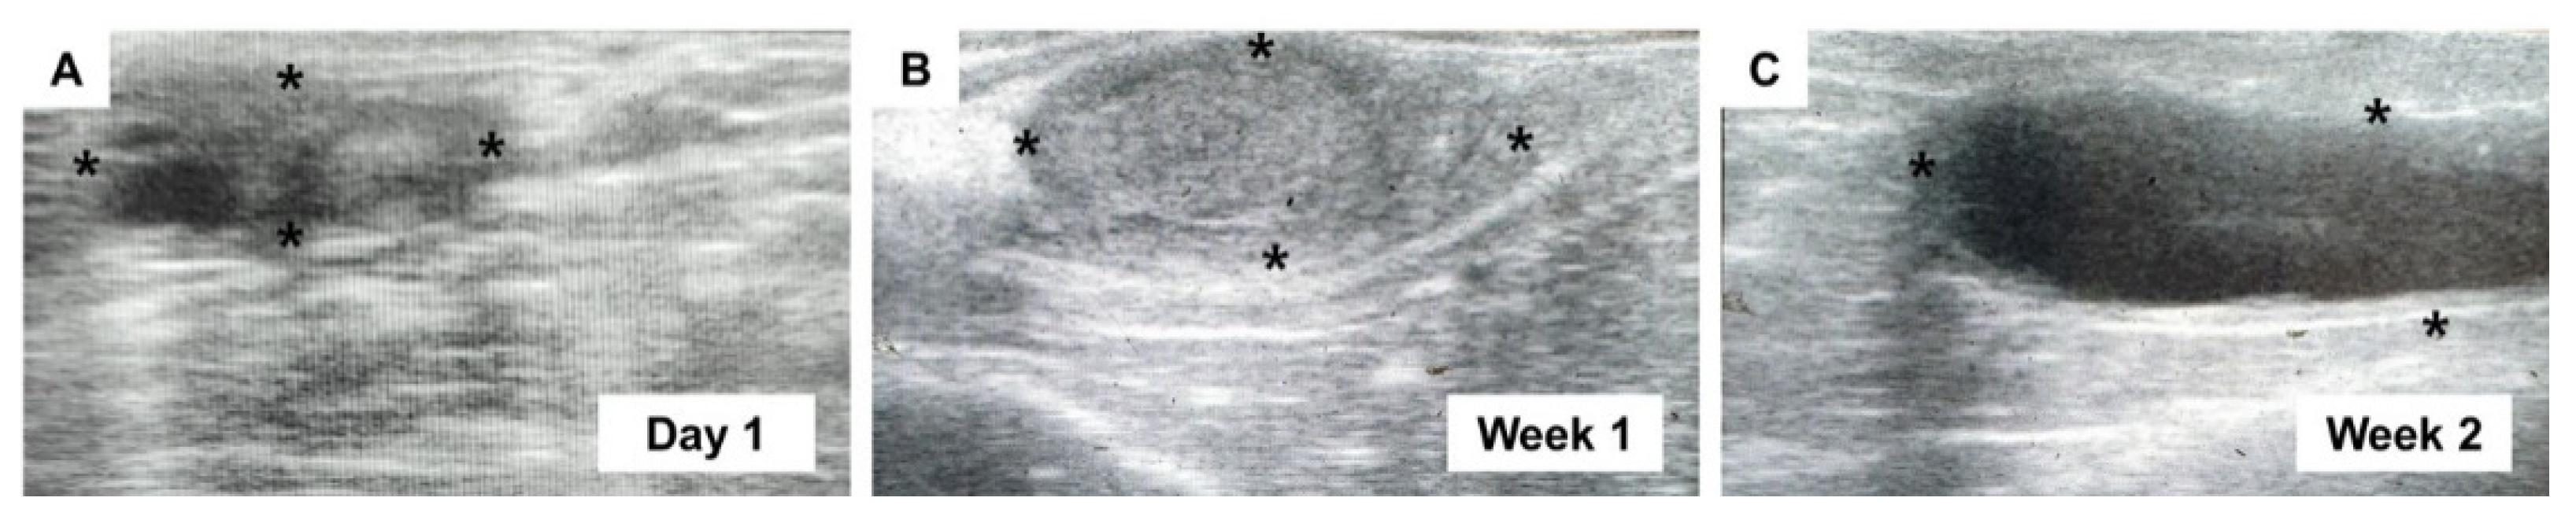

The ovaries of spayed heifers were scanned using transrectal ultrasound on day 1 prior to the surgery and at weeks 1, 2, and 4 post-surgery (Figure 1). The normal prepubertal ovary at day 1 had a major axis diameter of 10.2 ± 3.1 mm with small follicles (Figure 1A and Table 2). At week 1, the diameter was markedly enlarged (16.2 ± 4.2 mm) without any indications of folliculogenesis (Figure 1B and Table 2). Massive ovarian edema and significantly more increased swelling (p < 0.05; 23.1 ± 7.5 mm) than on day 1 appeared in hypoechoic images at week 2 (Figure 1C and Table 2). As shown in Table 2, most of the ovaries were palpable until week 1 after surgery, but approximately half of them only remained palpable at week 2. At week 4, ovaries were no longer palpable in the appropriate position, indicating that the infarcted and necrotic ovaries had dropped into the abdomen.

Figure 1. Periodical transrectal ultrasonography at postoperative observation period. Ultrasound scanning to ovaries at day 1 prior to surgery (A), and week 1 (B) and week 2 (C) after surgery. The image for week 4 is unavailable due to dropped ovaries into the abdomen. Asterisks indicate the margin of ovaries.